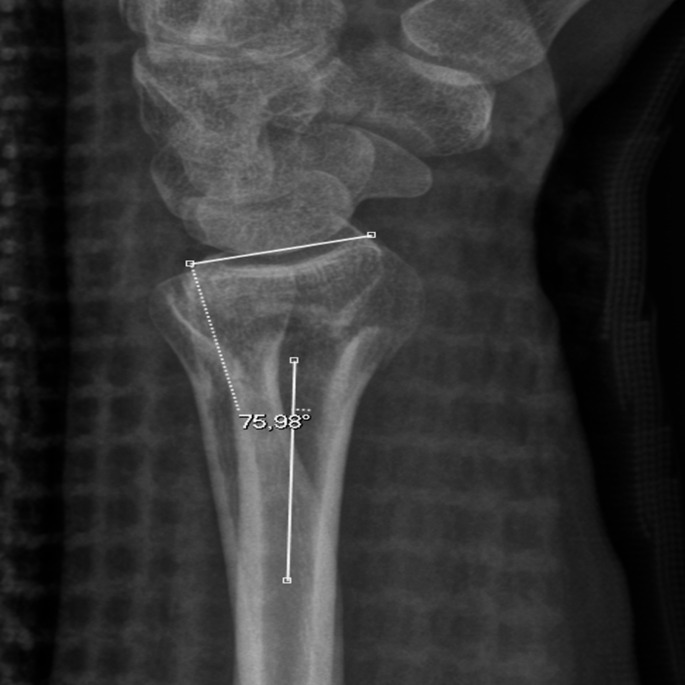

桡骨远端骨折是最常见的骨折类型之一。侧位x线片评估的桡骨远端关节面背侧倾斜常用于确定正确的治疗方法。本报告旨在强调在获得桡骨远端x线片时正确前臂定位的重要性,以及旋前和旋后对桡骨背侧倾斜测量的影响。它提出了一个病例35岁的男性与运动相关的跌倒期间持续的左侧桡骨远端骨折错位。

Distal radius fractures are one of the most prevalent fracture types. Dorsal tilt of the articular surface of the distal radius as assessed on the lateral radiograph is often used in determining the correct treatment method. This report seeks to highlight the importance of correct forearm positioning when obtaining distal radius radiographs, and the effects of pronation and supination on dorsal tilt measurements of the radius. It presents a case of a 35-year-old male with a malaligned left-sided distal radius fracture sustained during a sports-related fall.